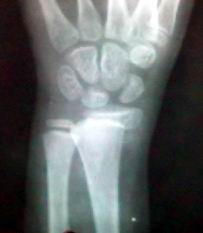

标题: X3837:腕关节外伤

骑自行车不慎摔倒,腕关节受伤

骺离骨折

桡骨远端骺离骨折.

典型

骨骺分离.骨密度低.半脱位.